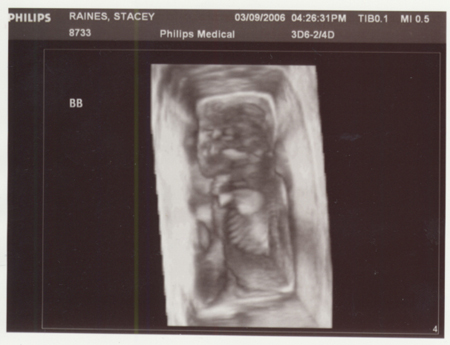

Yep, TWINS!! And if you think trying to tell the difference above now is difficult, just wait until July/August when you can hold them.

Nope, they are not identical, they are fraternal. So this can be a picture of two girls, two boys or one of each. So congrats to all you Grandma, Grandpa, Aunt, Uncle and cousins out there...